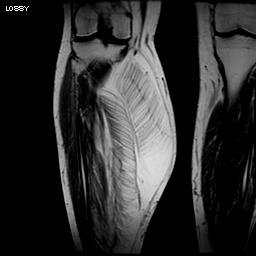

MRI

Same signal intensity as surrounding fat

Intra-muscular lipoma